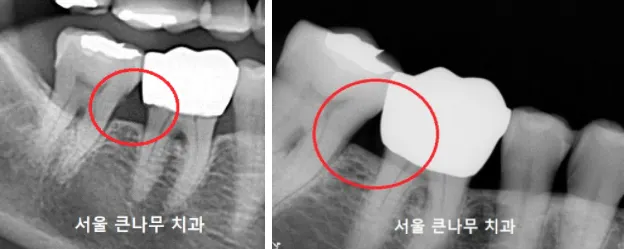

마찬가지로 치아 뿌리에 자리 잡고 있는 치석을 제거하였습니다. 스케일링만으로는 제거되지 않는 치석입니다.

좁고 깊은 부분은 칫솔이 잘 닿지 않아 음식물이 잘 끼기 쉬운 환경입니다. 치아 사이에 공간이 큰 부분일수록 치간칫솔을 이용하여 깨끗하게 관리해 주셔야 합니다.